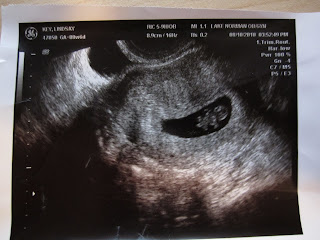

August brought our first doctor's appointment where we got to see our little nugget for the first time.